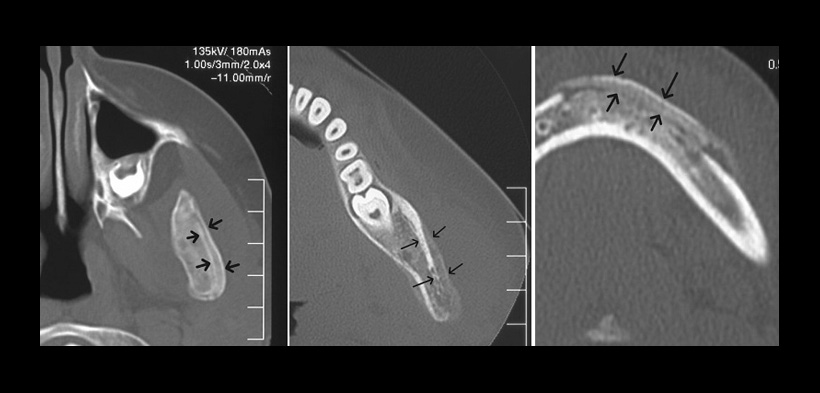

La tomografía computarizada (TC) es un método tridimensional eficaz para la evaluación de los cambios óseos, sin embargo implica la exposición de alta radiación en pacientes jóvenes. La tomografía volumétrica de haz cónico (CBCT), si está disponible, se debe considerar de primera elección por encima de la tomografía médica para la evaluación de posibles sospecha de OMRC, pues la información tridimensional tan precisa se obtiene a una dosis significativamente más baja (fig.2). La resonancia magnética (RM) es también una alternativa más segura, pero parece ser menos sensible a los cambios inflamatorios como los cambios óseos que se presentan en la enfermedad(1).

Fig. 2. Imágenes axiales de la tomografía computarizada cone beam (CBCT); todos los que muestran un patrón de » de hueso con hueso » (flechas)